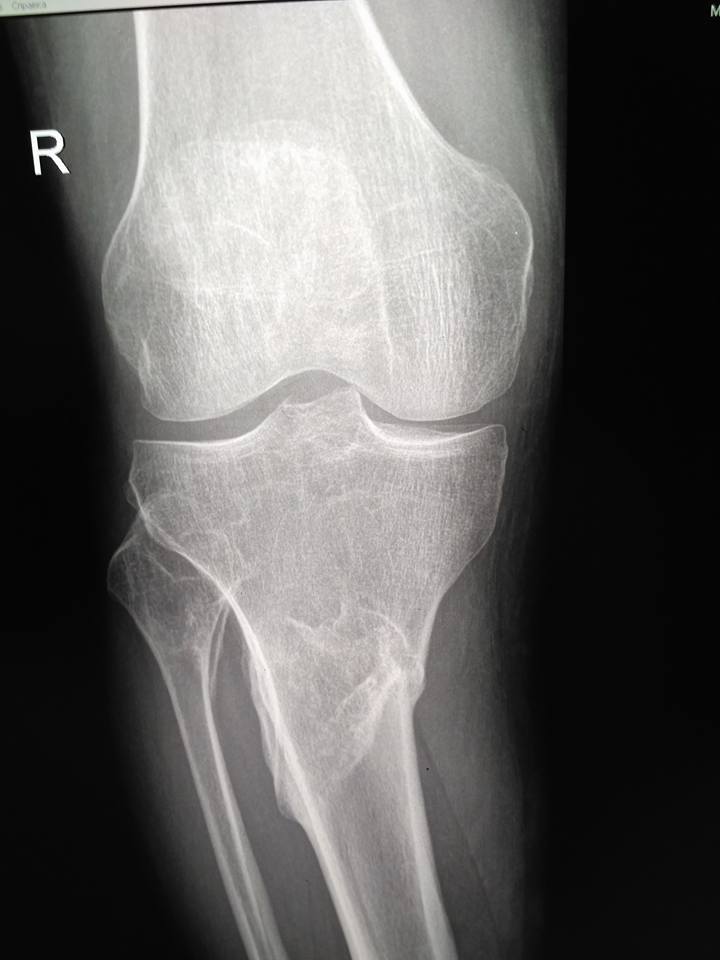

[Ortho] Псевдартроз tibia с варусной деформацией

Пациент мужчина 40 лет. Около 2-х лет назад травма. Лечили со слов

пациента гипсом, не было страховки, прописки и все было отягощено

хр.алкоголизмом.

Сейчас пациент встал так сказать на путь истинный, не пьет больше года,

выправил документы и хочет прямую ногу.

В области перелома в нижней трети подвижности практически нет, нога опорная.

Коллеги, какие мнения? Вопрос, стоит ли попытаться одномоментно

исправить ситуацию стержнем или растянуть сразу не удастся? Стоит ли

делать коррекцию в верхней трети?